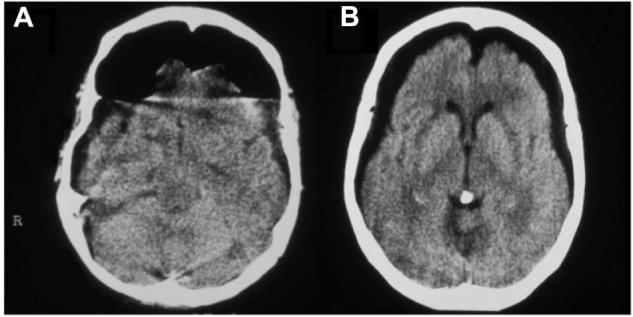

Clinical improvement was seen in all patients. In the treated group, a decrease of the gas bubble was observed on the computerized tomography scan after each session of HBO2. The treated group also experienced a lower rate of meningitis compared with the control group. The length of hospital stay was significantly higher in the control group compared with the treated group.

https://cdn.ncbi.nlm.nih.gov/pmc/blobs/4877/4199555/e41ba0b74385/tcrm-10-769Fig1.jpg